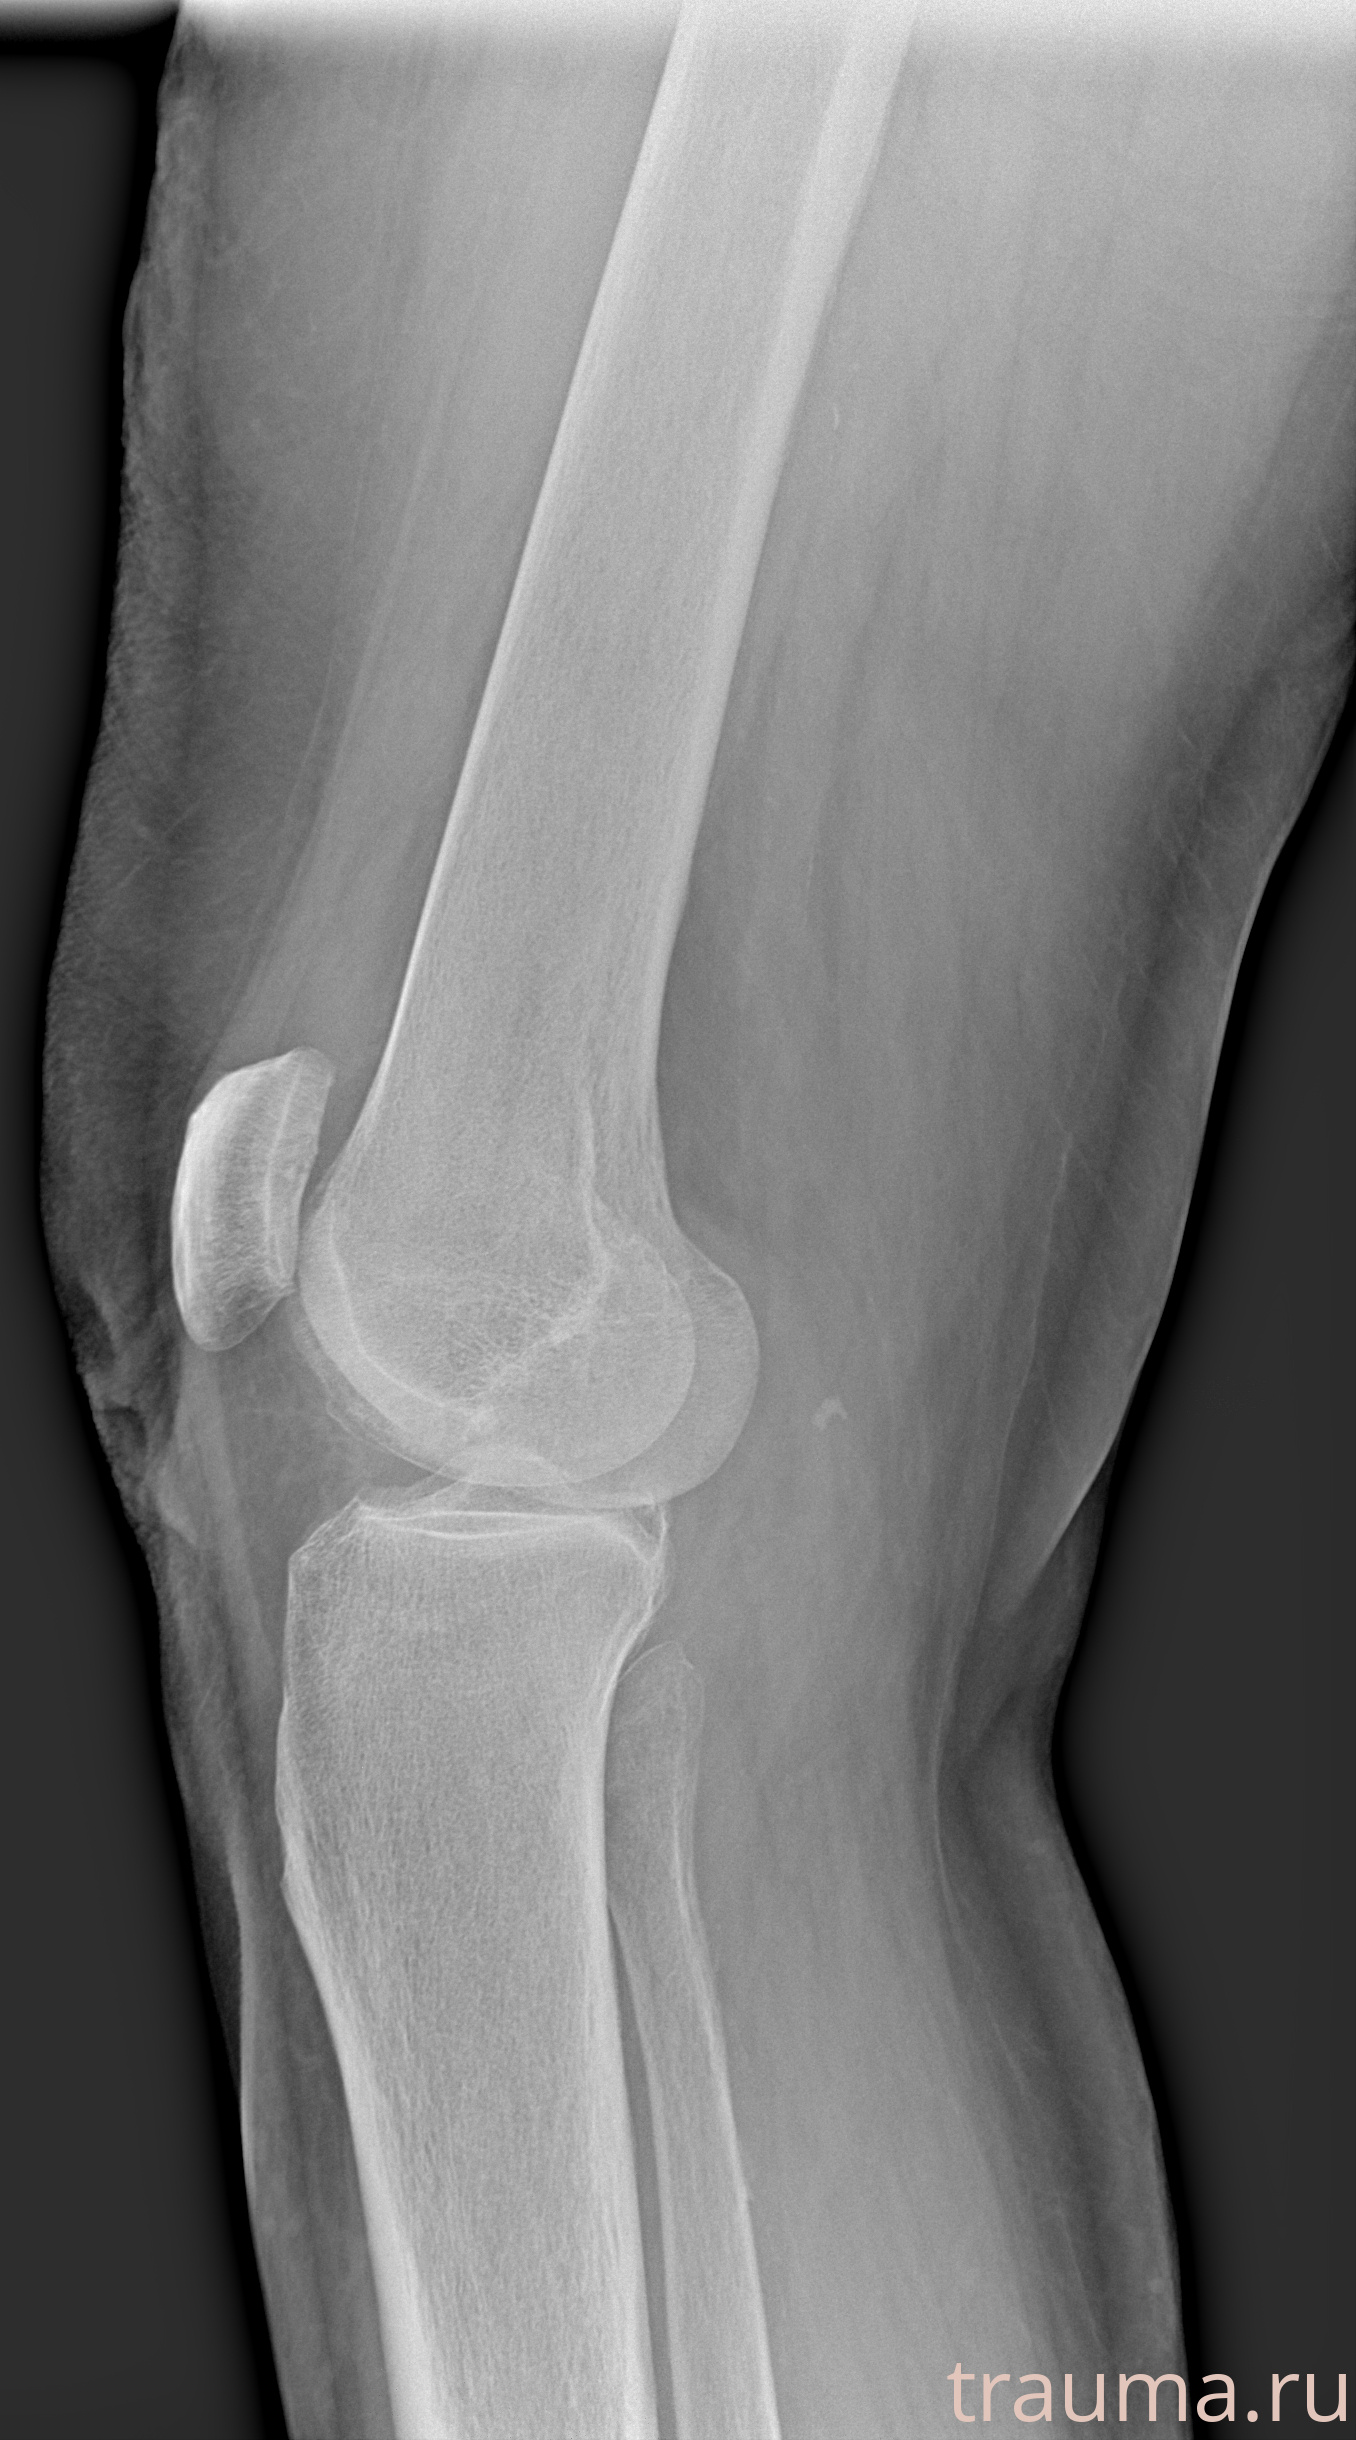

Левая

Рентгенограммы

Рентген на дому: по вашему адресу приезжает врач-рентгенолог, травматолог-ортопед с мобильным рентгеновским аппаратом, проводит диагностику травмы или заболевания, делает необходимые рентгенограммы, дает рекомендации по дальнейшему лечению. Получить качественные снимки в домашних условиях возможно благодаря уникальной методике, разработанной МосРентген Центром для института  Склифосовского